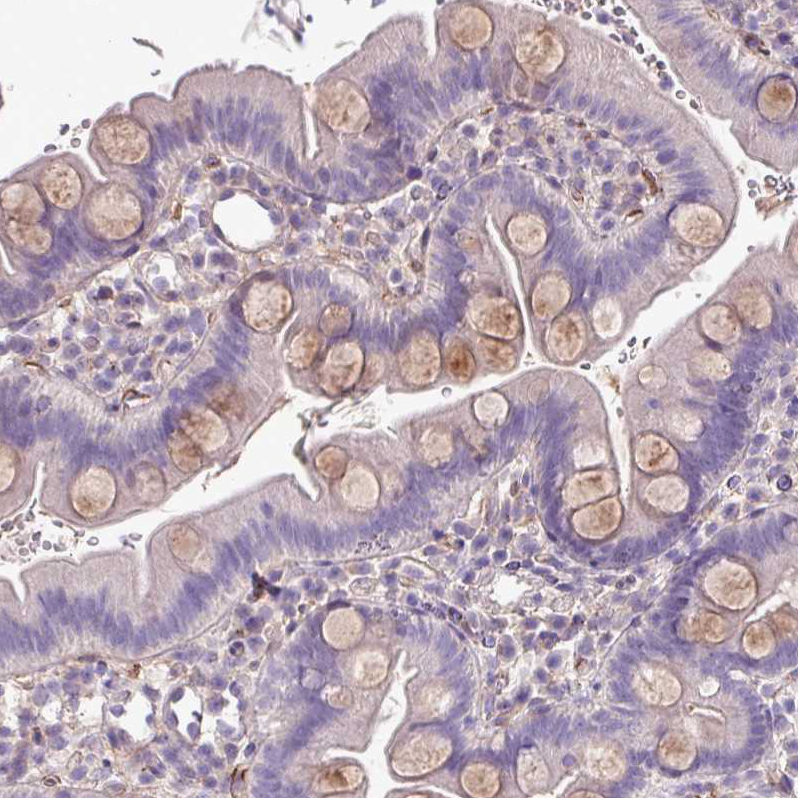

Immunohistochemistry analysis in human placenta and liver tissues using HPA051856 antibody. Corresponding CD248 RNA-seq data are presented for the same tissues.